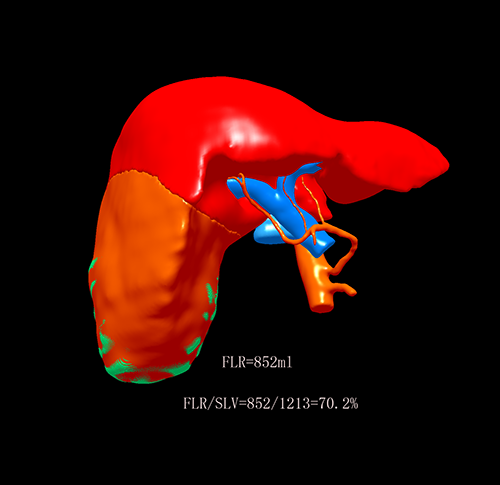

右肝癌-腹腔镜S56肝切除